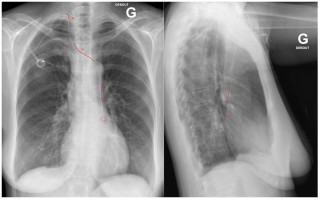

We report the case of a 17-year-old previously healthy male who developed sudden severe dyspnea while recreational skiing at a moderate altitude of 2'200 meters. On-site emergency management required immediate bilateral needle decompression, followed by urgent transfer to hospital care. Imaging confirmed a complete bilateral pneumothorax with bilateral apical subpleural blebs (Figure 1). Sequential bilateral chest tube placement was performed, and the patient subsequently underwent staged bilateral video-assisted thoracoscopic surgery with apical wedge resection and mechanical pleurodesis. Postoperative recovery was uneventful, with no recurrence during follow-up. Etiological investigations revealed normal alpha-1 antitrypsin levels. Transthoracic echocardiography identified a bicuspid aortic valve associated with moderate aortic regurgitation (grade 2/4). Combined clinical, radiological, and cardiac findings ultimately led to the diagnosis of Marfan syndrome, previously unrecognized.